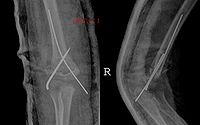

既往有外傷史,而傷後又未作任何處理,尤其是關節附近軟組織損傷。如常發生於肱肌,則表現為肘關節區腫脹、壓痛,肘關節被動主動活動受限。隨後疼痛與腫脹消退,在肘關節前方可摸到一個包塊,因包塊出現而肘關節功能受到影響。另外也可見於三角肌、內收肌。

骨化好發與肱肌,表現為肘關節區腫脹與疼痛,肘關節被動與主動活動均受限。疼痛與腫脹減退後在肘關節前方可以摸到一個界線清楚的硬的腫塊。因肌肉無彈性,故肘關節伸屈受限;由於腫塊的阻擋,屈曲也明顯受限。